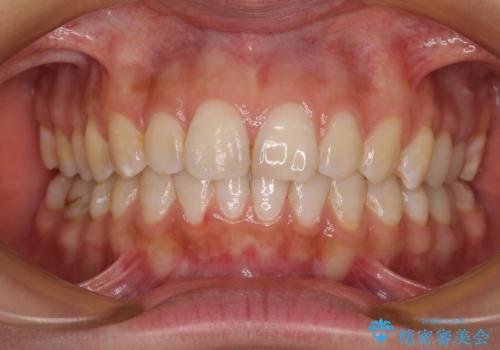

費用を抑えた抜歯矯正 口元の突出感の改善

左側の咬み合わせと上下正中の位置をコントロールするために時間がかかりましたが、事前に思い描いた通りの歯列に整い、患者様には大変満足していただきました。